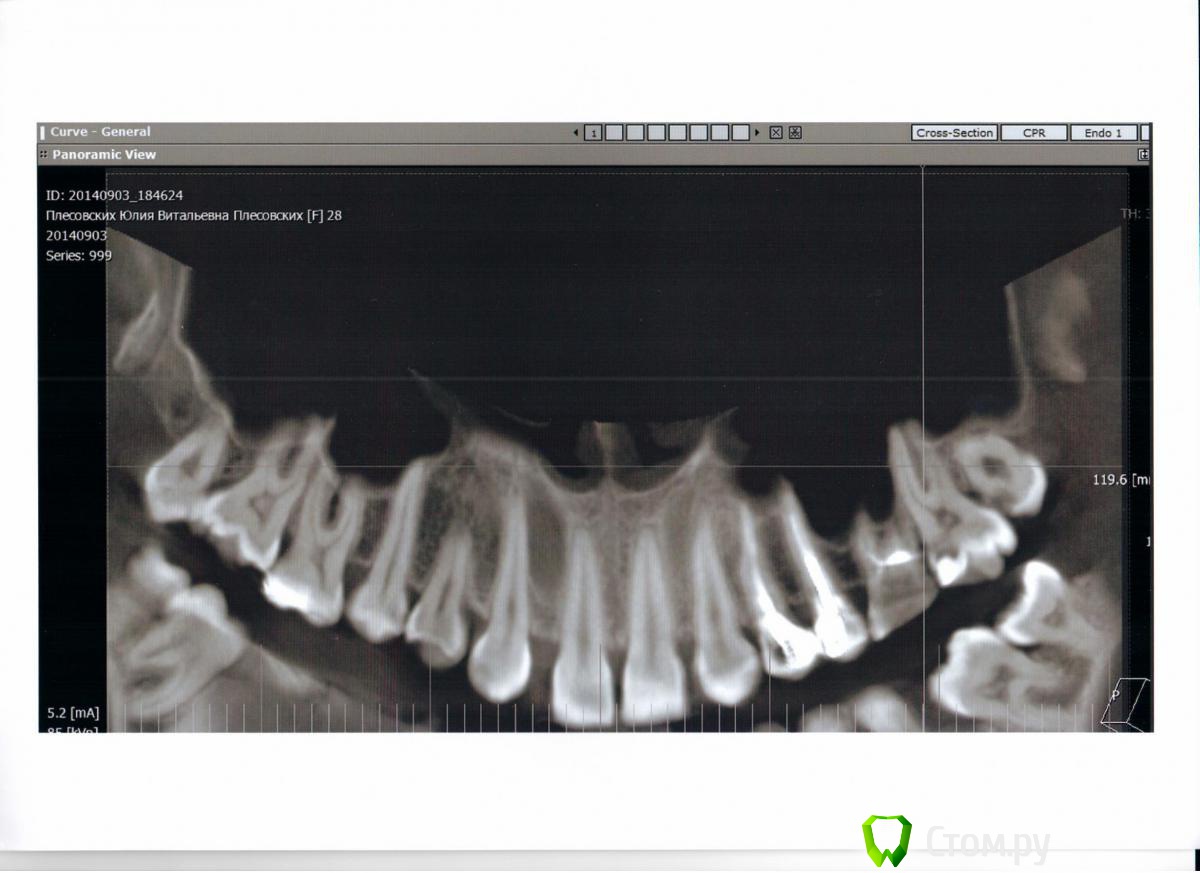

Julia_86 Опубликовано 9 сентября, 2014 Поделиться Опубликовано 9 сентября, 2014 Здравствуйте, прошу совета по дальнейшему лечению. Не знаю верно ли разместила тему, поправьте если что не так.Месяца полтора назад случайно обнаружилась радикулярная киста нижних передних зубов. Хотела поставить брекеты по причине адентии верхних двоек, врач отравил на понорамный снимок - увидели кисту. Зубы, которые охвачены кистой, никогда не болели, но один из зубов изменен в цвете и видимо был травмирован,т.к. видно скол. Терапевт сначала хотела лечить через каналы, закладывая лекарство на полгода, но я засомневалась и пошла к хирургу. Хирург отправила на КТ. В итоге хирург после КТ решила, что центральный резец в кисте нужно удалять(он короче всех) и делать операцию одновременно. Во время операции заложить костнозамещающий материал (bio-oss) и ждать пока все восстановиться.Но есть один момент - чтобы остальные 2 зуба, которые в кисте, не выпали, врач предлагает или поставить брекеты перед операцией, чтобы они не давали зубам шевелиться после операции. Позже, когда все зарастет и костная ткань восстановиться - брекетами восстановить зубной ряд из 3х резцов. Сейчас на нижней челюсти скученность, после удаления как раз хватит места для 3х зубов. Либо до операции клеить какую-то штуку на внутреннюю сторону зубов и после операции через 4 месяца протезировать. Зубы, которые в кисте будут депульпированы и запломбированы. Подскажите, какой вариант более целесообразен. Ссылка на комментарий

dr-krasnov Опубликовано 9 сентября, 2014 Поделиться Опубликовано 9 сентября, 2014 Это не радикулярная киста. Стоит подумать о дисплазии. Что скажут коллеги? 1 1 Ссылка на комментарий

Bier Опубликовано 10 сентября, 2014 Поделиться Опубликовано 10 сентября, 2014 Автор, сфотографируйте нижние зубы пожалуйста.Не надо торопиться с хирургией.План действий такой: определить витальные (живые) ли зубы, находящиеся в полости кисты. Скорее всего потемневший зуб мертв. Тогда надо провести терапевтическое лечение, через канал, желательно только терапевта поискать с микроскопом.Если все зубы живые, как предположил коллега, тогда к хирургу с обязательной гистологией образования. 1 Ссылка на комментарий